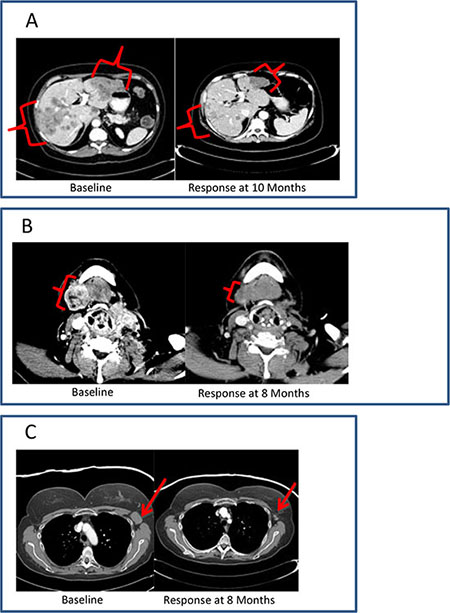

Among patients with breast cancer, cutaneous metastases, nodal metastases, and visceral disease were all observed to respond to therapy (Figure 2). Transient inflammatory responses were observed in a few patients before an objective response was observed.

Figure 2: Clinical vignettes. (A), diagnosis: hormone receptor positive breast cancer; previous treatment: 6 lines of systemic therapy; best response: PR; duration of therapy: 12 months. (B), diagnosis: initially ER+, Her-2- breast cancer, with subsequent development of triple-negative metastatic disease; previous treatment: 5 lines of systemic therapy; best response: PR; duration of therapy: 12 months. (C), diagnosis: triple-negative breast cancer; previous treatment: 7 lines of systemic therapy; best response: PR; duration of therapy: 9 months.